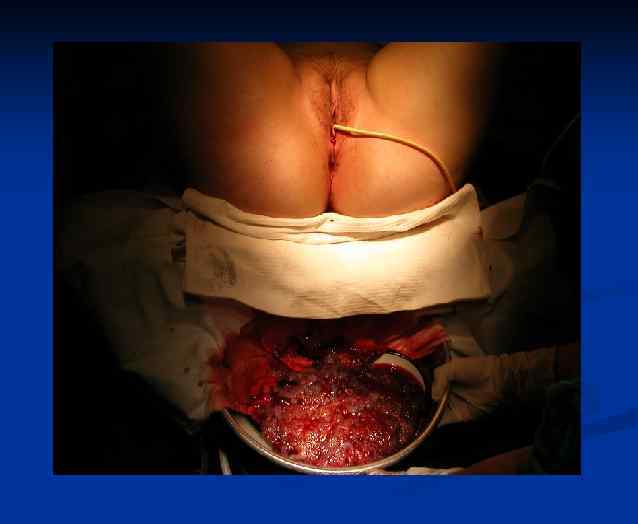

ОПЕРАЦИЯ Лапаротомия. Экстирпация матки без придатков.

Ход операции Лапаротомия

Операционный препарат при хориокарциноме